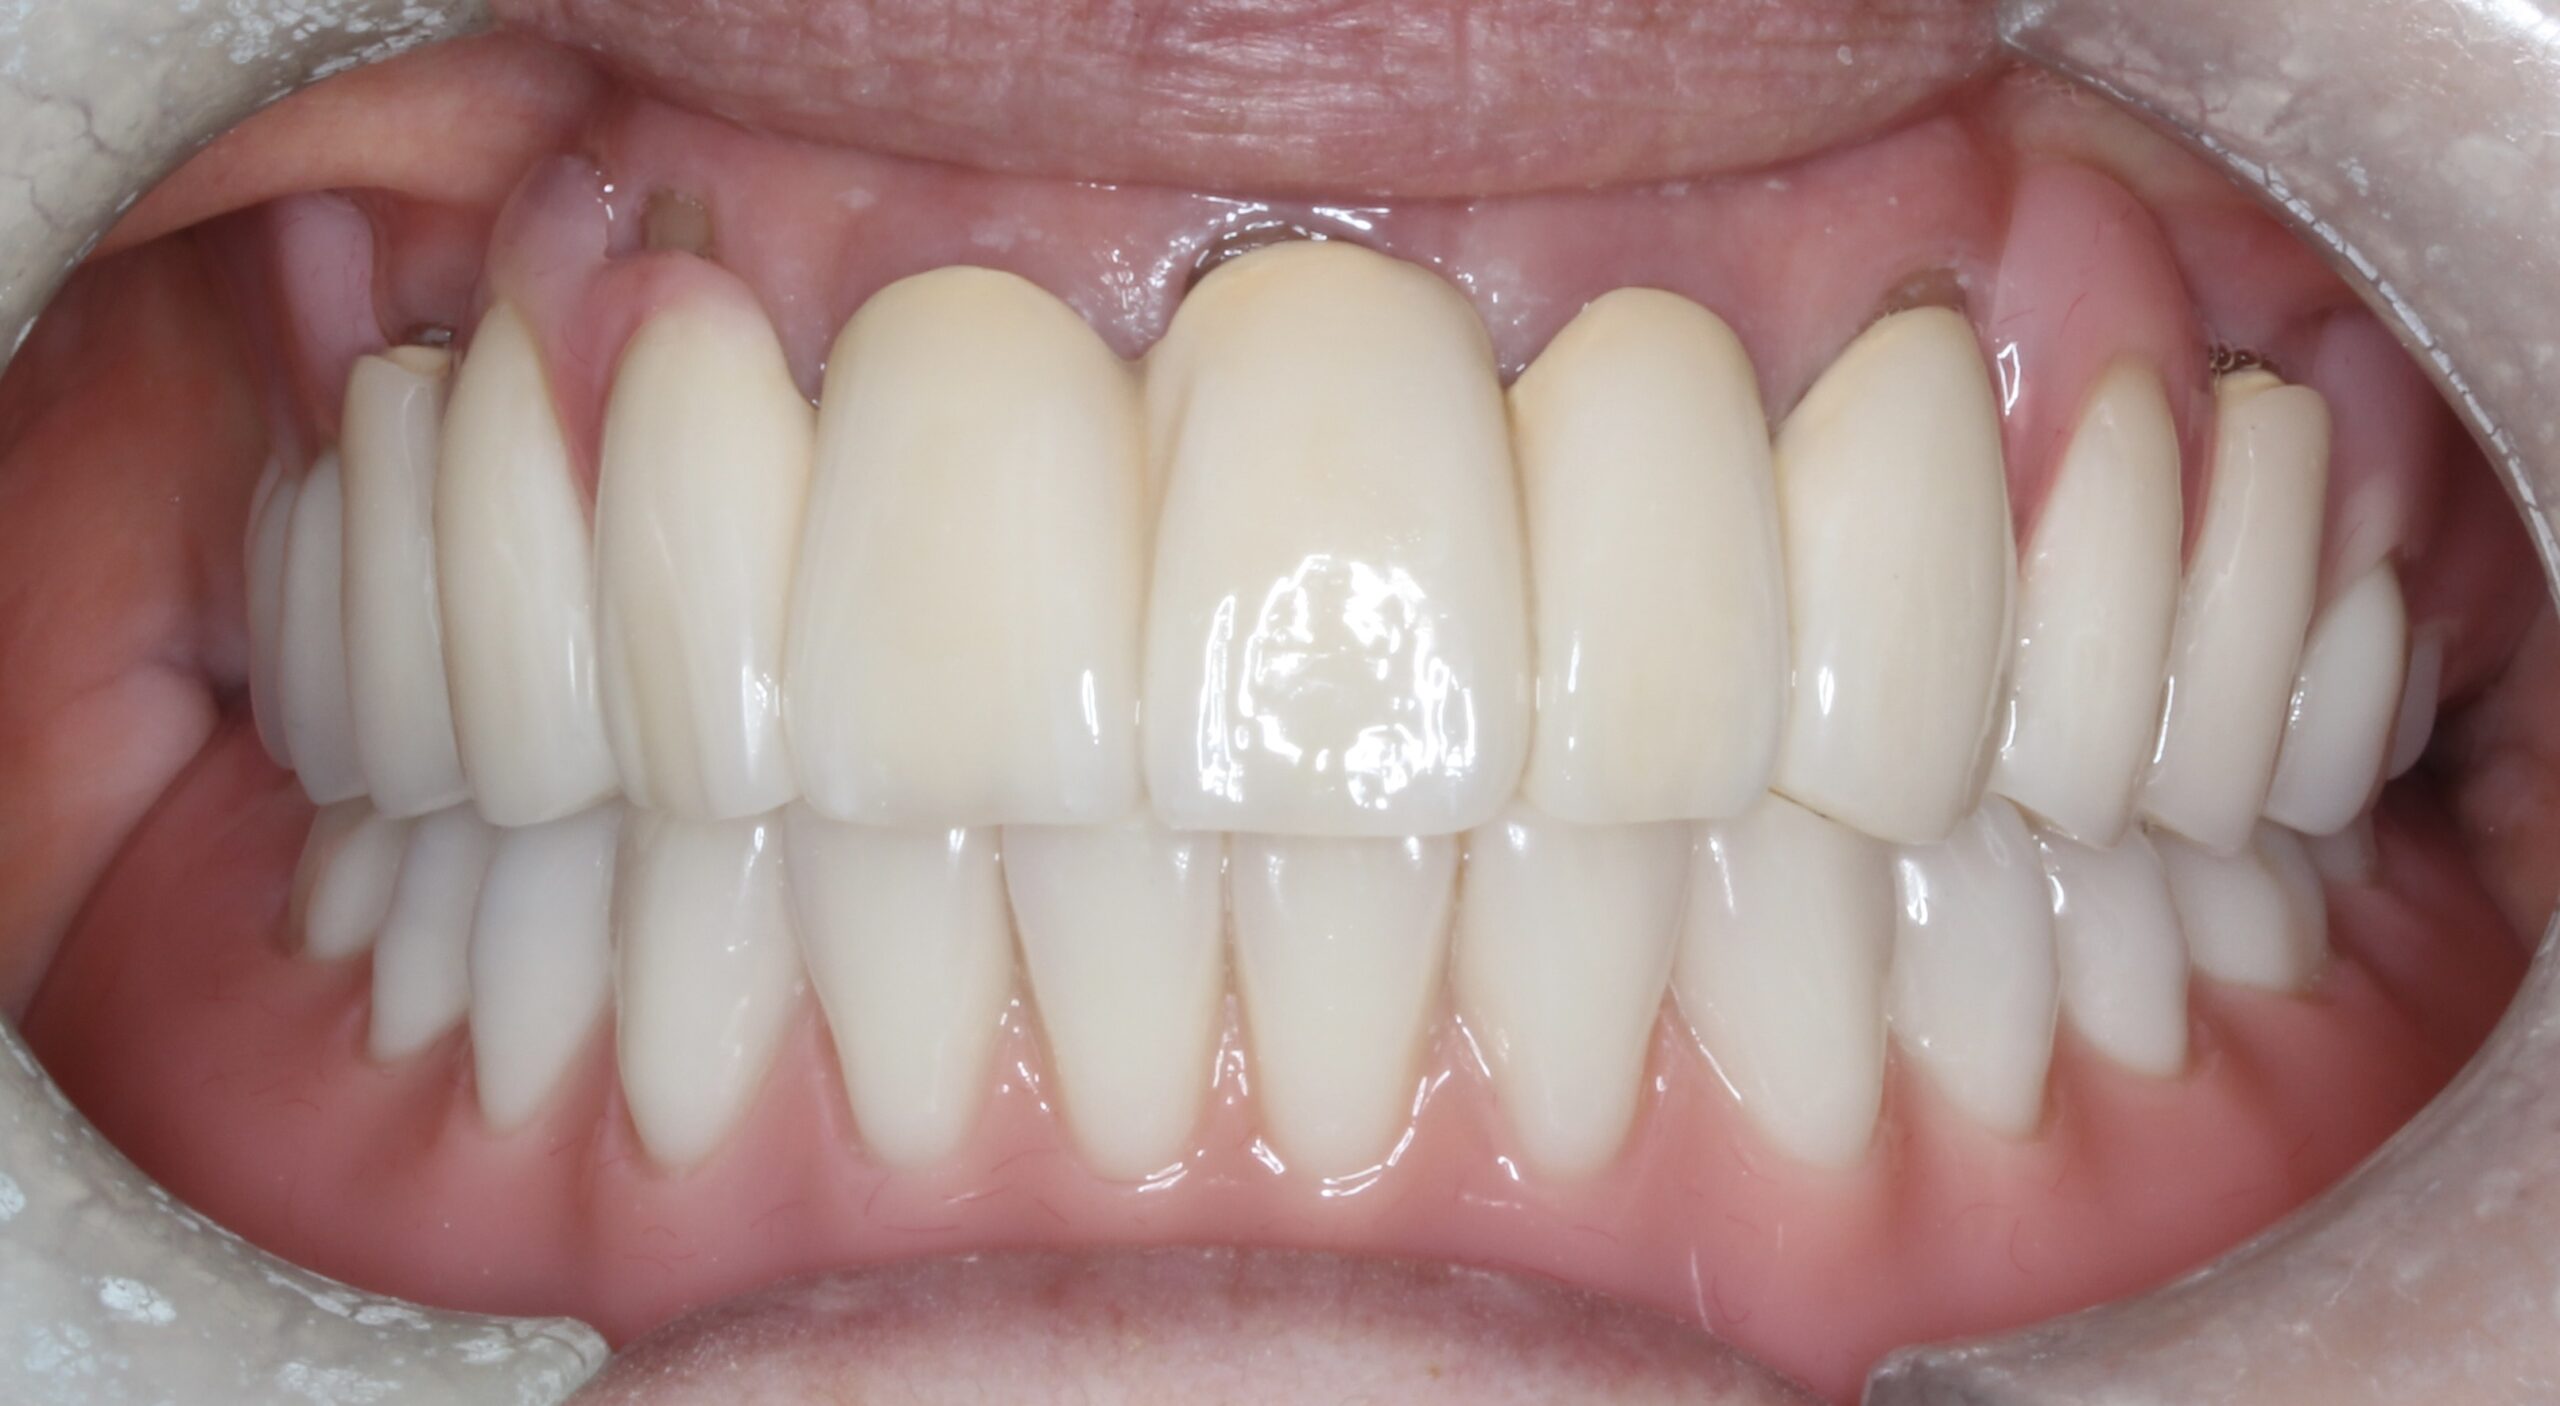

上顎はコーヌステレスコープ、下顎はレジリエンツテレスコープにて治療を行なった。

【治療後】